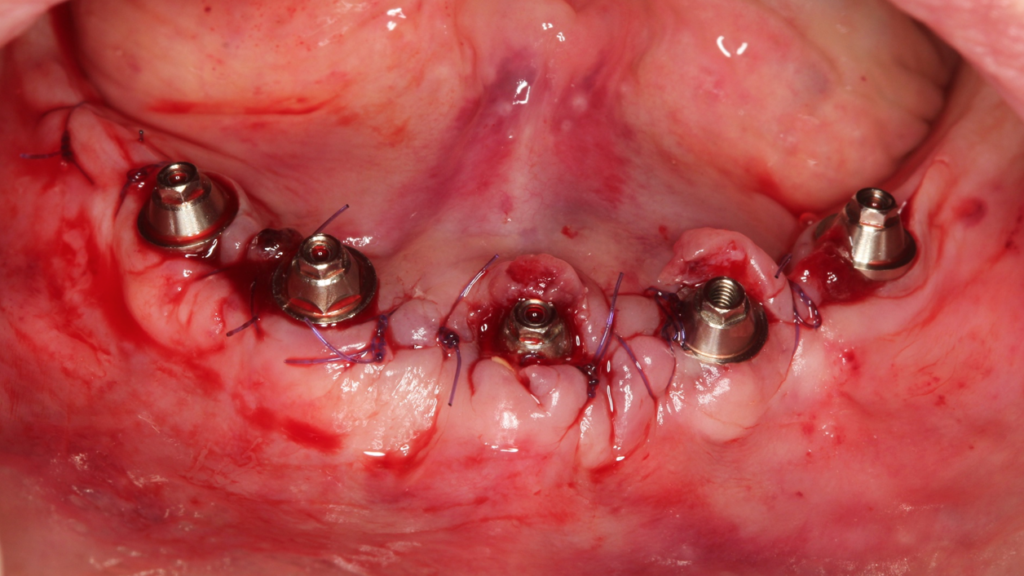

A seguir, vamos ilustrar um caso de cirurgia com 2 guias ósseos, 1 de recorte ósseo e outro de perfuração:

Paciente do sexo feminino, 82 anos, com a presença de dentes anteriores de mandíbula usando prótese móvel na região posterior por mais de 30 anos. Com isso, a reabsorção óssea posterior causou um desnível muito grande em relação à região anterior.

Através do programa Blue Sky (em parceria com a empresa Odontoplanning), foi feito planejamento guiado com 2 guias. O primeiro guia de recorte ósseo, tem como objetivo o recorte e aplainamento ósseo, deixando uma altura óssea mais uniforme entre a região posterior e anterior da mandíbula.

Através da imagem do osso recortado é planejada a guia de perfuração que vai se encaixar de uma maneira perfeita no osso recortado.

Lembrando que essas guias serão apoiadas exclusivamente no osso, sem envolvimento de mucosa, portanto há que se fazer incisão e descolamento mucoperiostal suficiente para o encaixe da guia.

O planejamento acima, foi feito para a instalação de uma prótese fixa aparafusada final, com estrutura metálica rígida e acrilização, no mesmo dia da cirurgia. A regularização do rebordo da paciente permitiu a instalação dos implantes em um posicionamento 3D ideal para uma reabilitação protética com os parâmetros biomecânicos, funcionais e estéticos adequados, transformando uma situação com várias limitações e dificuldades em um caso favorável, de uma maneira simples e previsível.